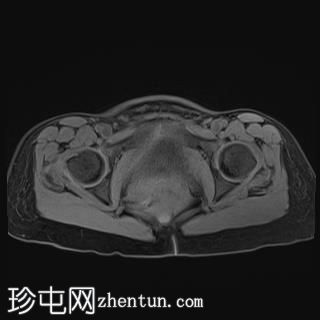

轴位T1加权像

脂肪抑制像

轴位

T1加权像

T1加权像平扫显示T1高信号,与CT上的高密度部分相对应,增强后无强化,符合血液成分表现。